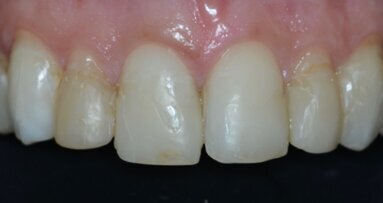

La paziente S.M. di anni 42, si presenta alla nostra osservazione per migliorare l’estetica del settore frontale (Fig. 1). All’esame obiettivo si ...